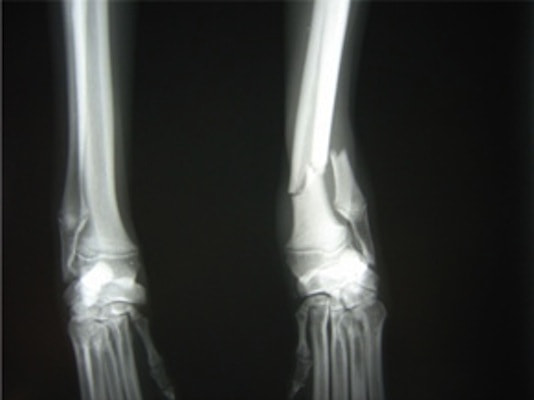

症例3:キルシュナーワイヤーのピンニングによる整復

ペルシャ猫 11ヶ月齢 雄

他院にて左大腿骨遠位の成長板骨折(salter-harrisⅠ型)が認められており、治療相談を目的として来院。当院にて、キルシュナーワイヤーを用いたピンニングにより骨折部位の整復を行いました。術後の経過は良好で、現在も経過観察中です。

術前レントゲン

術後レントゲン